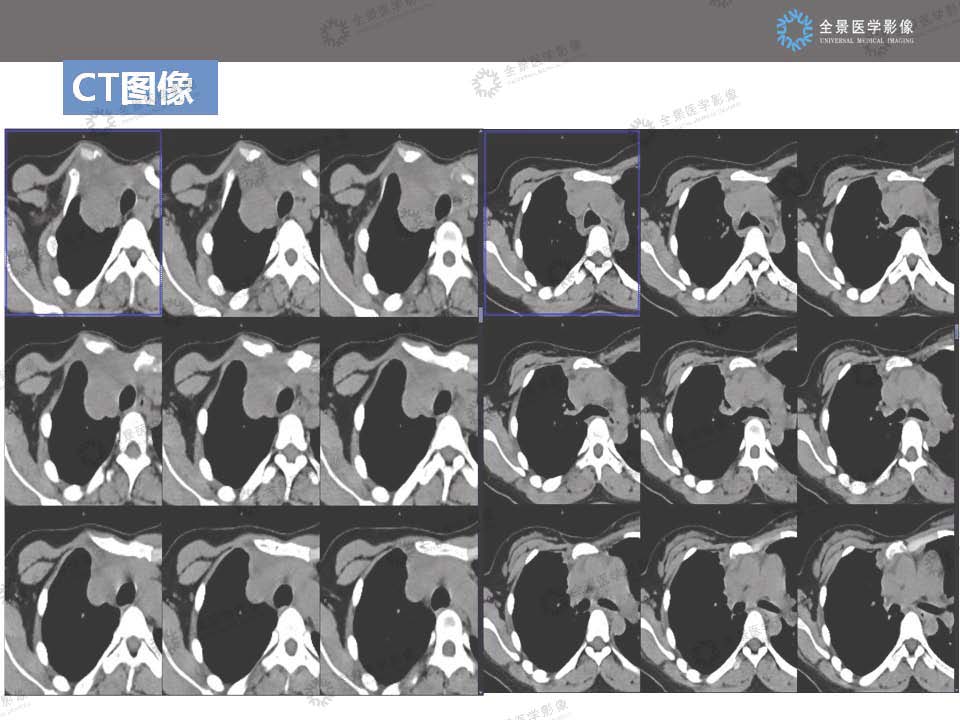

神经鞘瘤读片病例